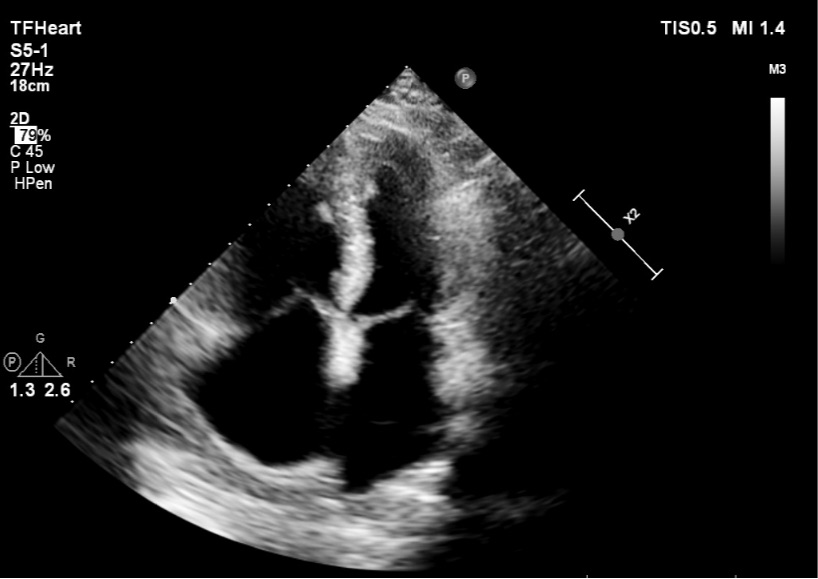

患者65岁,定期体检,自觉身体健康状况良好,既往无心脏疾病史。本次因前列腺疾病入院,在完善术前检查时,胸部CT却显示心脏明显增大,肺动脉及其分支明显增粗,提示肺动脉高压可能。这个异常信息立即引起了主管麻醉医生黄焜的关注,于是安排患者进行了心脏彩超检查。心脏彩超显示:房间隔中份回声失落27*23mm,房间隔缺损(继发孔型)房水平左向右分流,左室收缩功能测值正常。

图:心脏彩超提示患者房间隔缺损